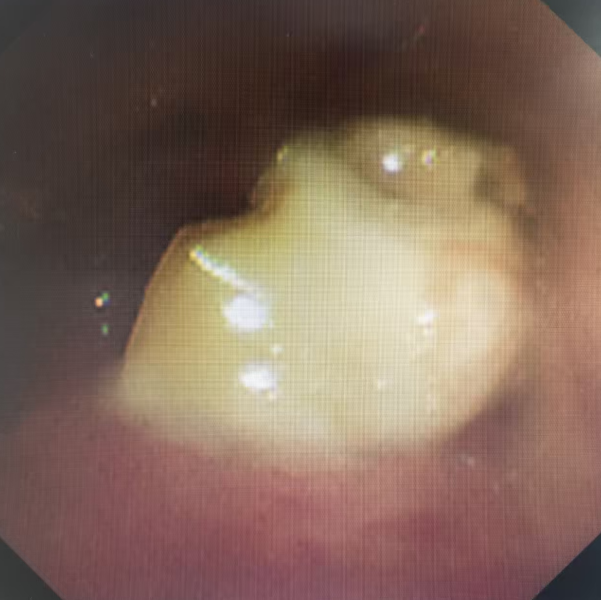

通过电子支气管镜,救治团队看到在宝宝细小的支气管深处,一颗已经被泡胀的花生死死地卡住,周围黏膜已经红肿发炎。医护人员默契配合,最终将这颗惹祸的元凶顺利取出。

△支气管镜下取出的花生异物